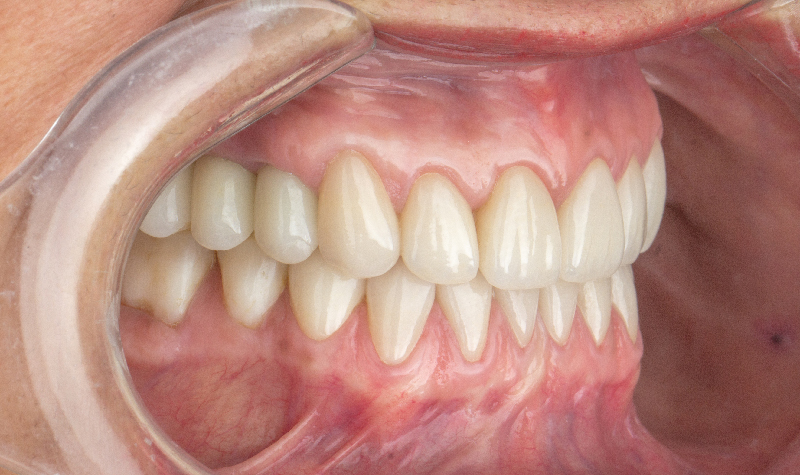

Prótesis híbrida superior de cerámica fija sobre implantes.

Prótesis híbrida superior de cerámica fija sobre implantes